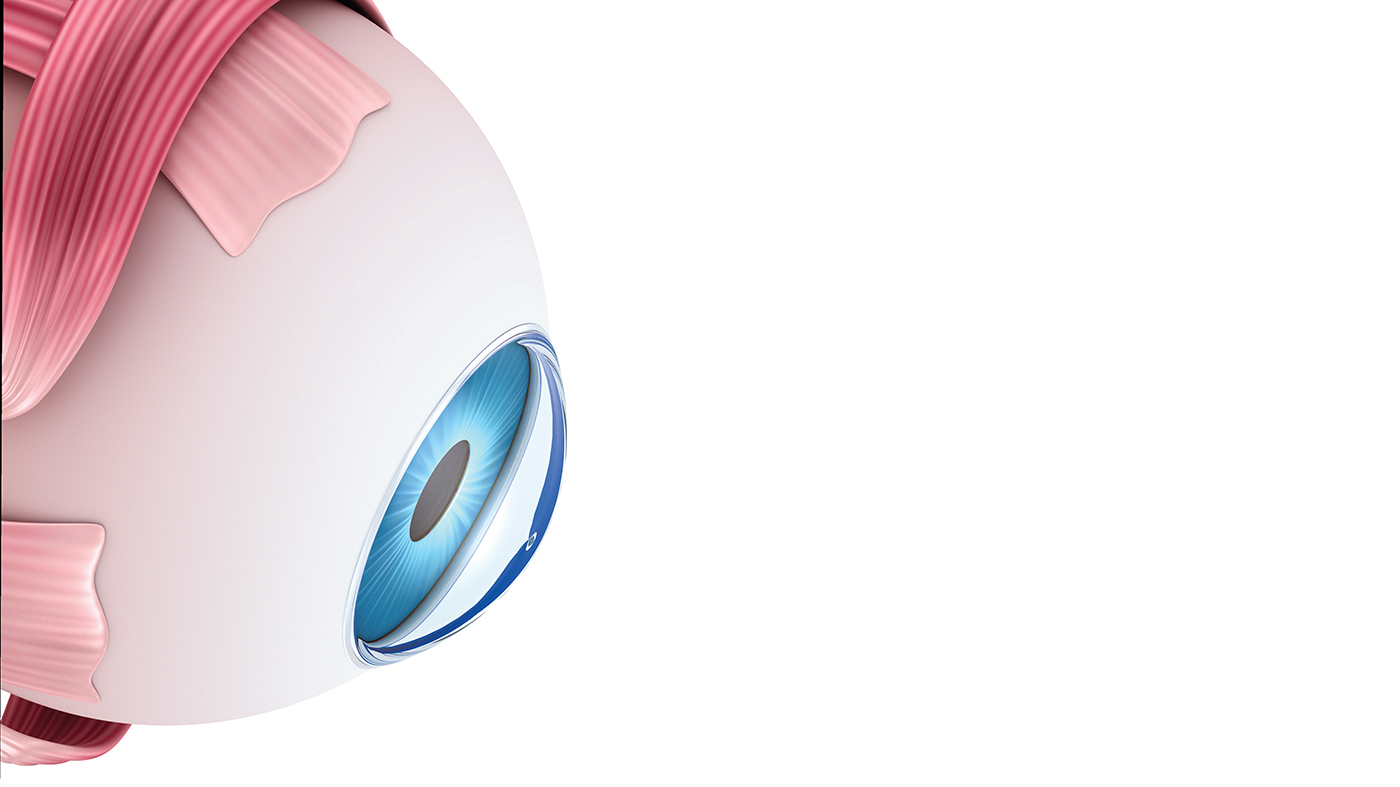

إن التهاب العصب البصري هو التهاب يتلف العصب البصري، والعصب البصري هو مجموعة من الألياف العصبية تنقل المعلومات البصرية من العين إلى الدماغ. يعد الألم وفقدان الرؤية المؤقت في عين واحدة من الأعراض الشائعة لالتهاب العصب البصري.

إن السبب الدقيق وراء الإصابة بالتهاب العصب البصري غير معروف. ويُعتَقد أنها تحدث عندما يستهدف الجهاز المناعي المادة التي تغطي العصب البصري (الميالين) عن طريق الخطأ؛ مما يؤدي إلى التهاب وتلف في الميالين.

عادةً ما يساعد الميالين في انتقال النبضات الكهربائية سريعاً من العين إلى الدماغ، حيث يتم تحويلها إلى معلومات بصرية. يعطل التهاب العصب البصري هذه العملية، مما يؤثر في الرؤية.